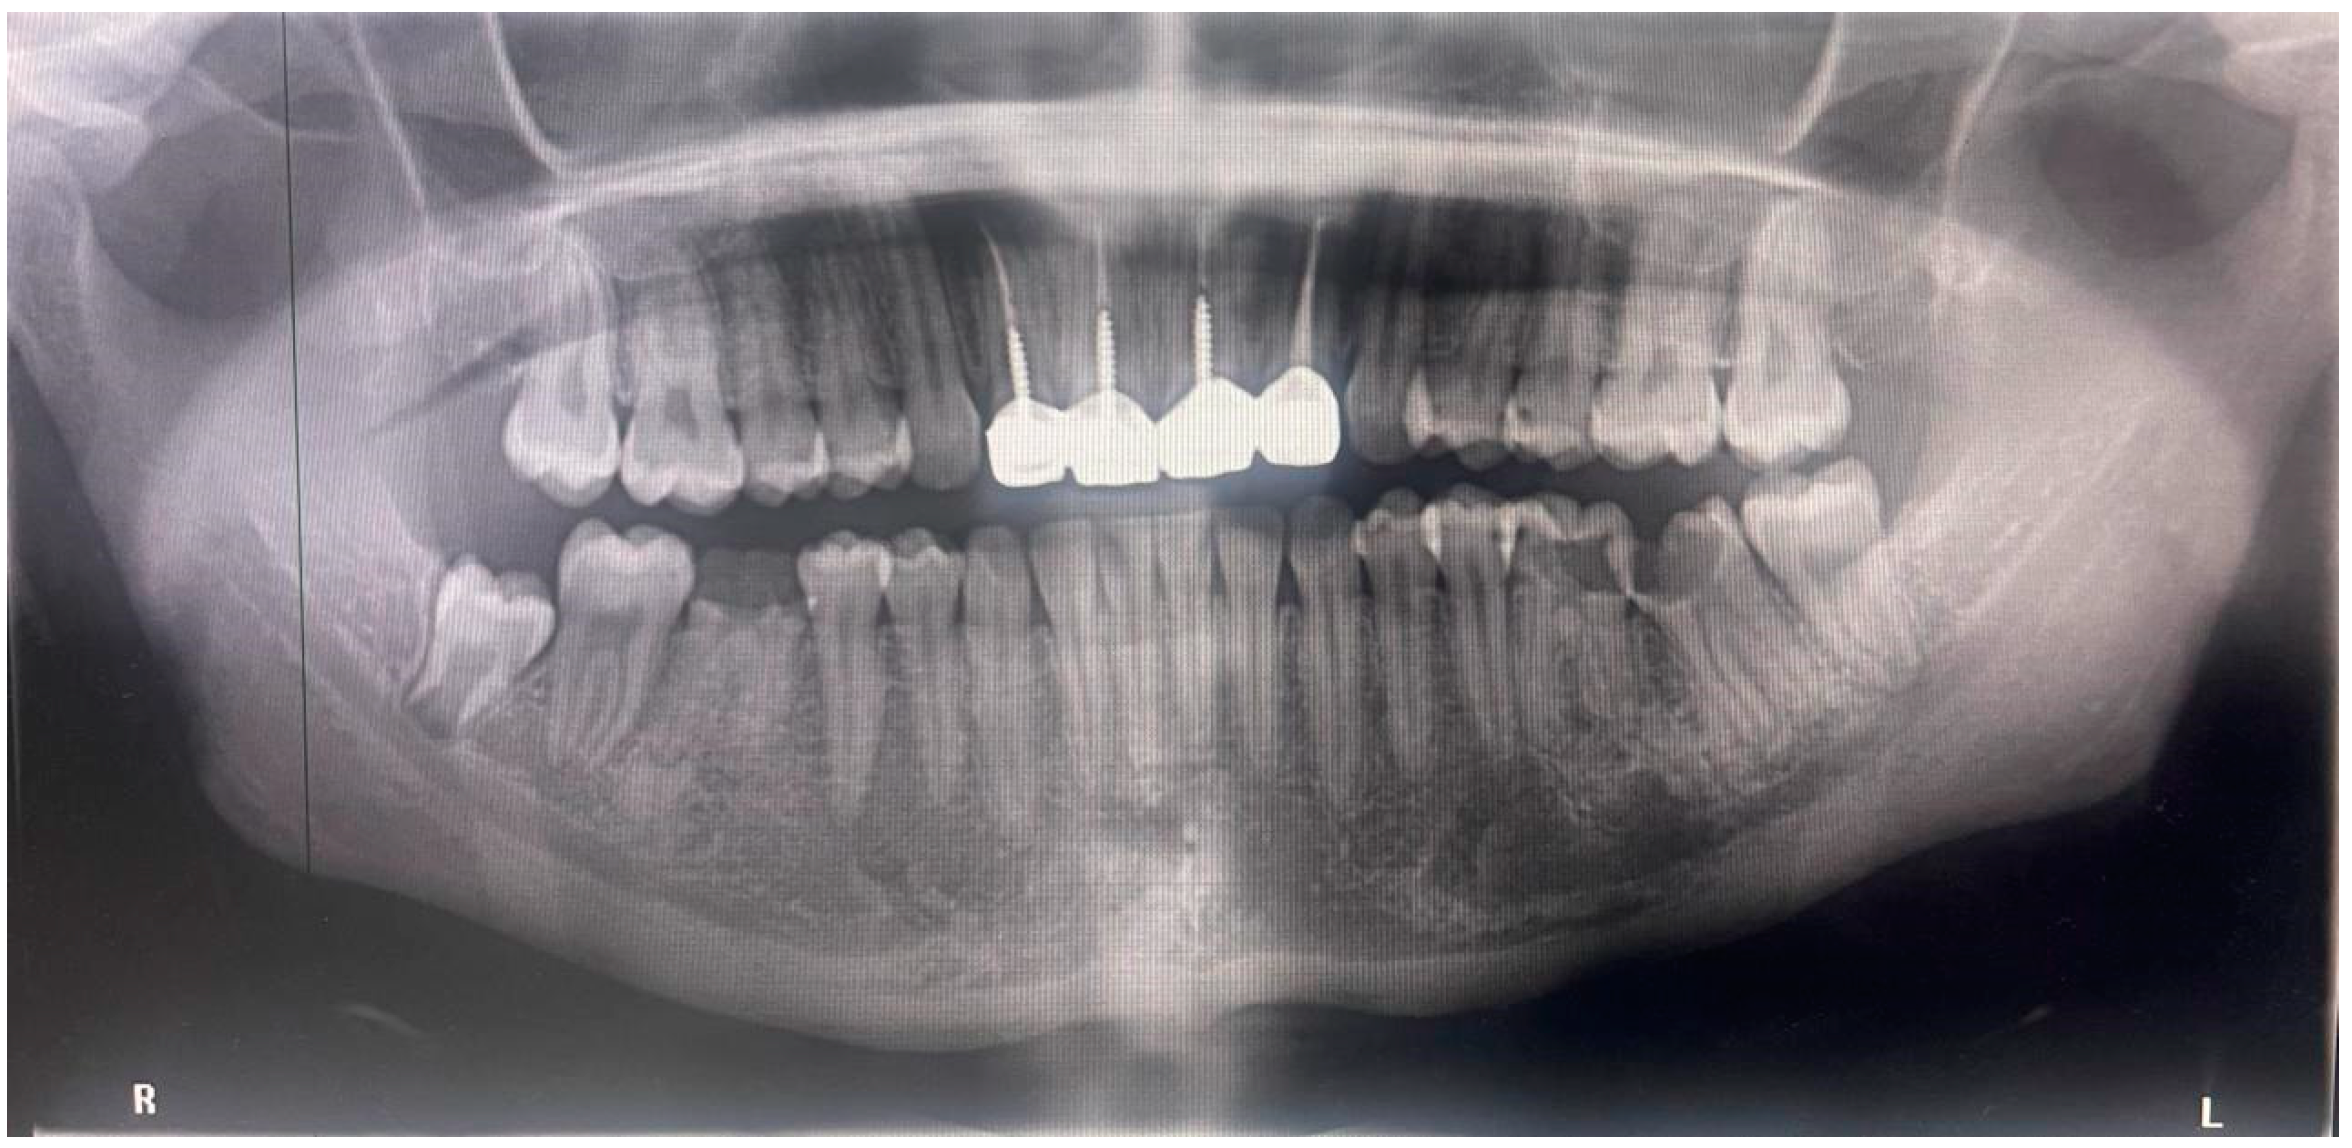

2.3. Radiographic Examination